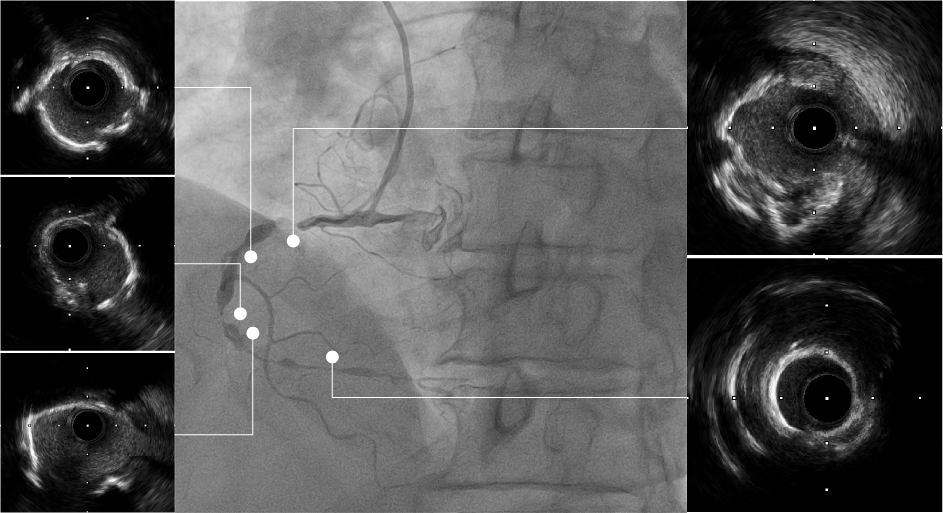

ROTA后评估

IVUS可见RCA近中段弥漫钙化病变,多>270°钙化环,3# 近端钙化壁较厚,可见旋磨后多重反射影;近中段病变扩张不充分,钙化环未见明显断裂,IVUS导管未能通过远端病变处。

IVUS无法通过远段

IVUS结果:远端钙化处可见360°钙化环断裂,多重反射影;远端血管直径约2.5mm。

再次IVUS评估

IVUS结果:可见近段及中段多处钙化环断裂,管腔狭窄明显改善;远端钙化环较厚未见明显断裂,管腔扩张不充分。

前后IVUS对比